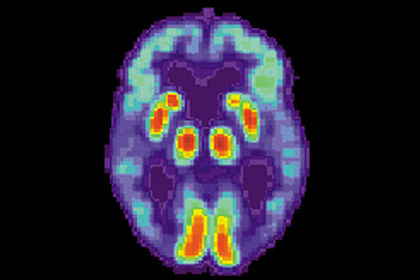

Жанубий Флорида соғлиқни сақлаш университети олимлари альцгеймер хасталигининг хавфли ва давоси йўқ тури билан касалланган беморларга ёрдам бериши кутилаётган вакцина яратишди. Бу ҳақда Lenta.ru нашри хабар берди.

Клиник синовлардан олдинги тадқиқотлар амилоид бета пептиднинг нейротоксик шаклларига қаратилган дентрит вакцина хавфсиз ва асаб ҳужайралари нобуд бўлишининг асосий сабаби ҳисобланган амилоиднинг қаттиқ қатламлари ҳосил бўлишига қарши иммунитетни шакллантиришини кўрсатди.